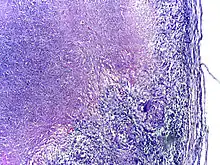

Microscopy of tuberculous epididymitis. H&E stain

TB infection begins when the mycobacteria reach the alveolar air sacs of the lungs, where they invade and replicate within endosomes of alveolar macrophages.[15][59][60] Macrophages identify the bacterium as foreign and attempt to eliminate it by phagocytosis. During this process, the bacterium is enveloped by the macrophage and stored temporarily in a membrane-bound vesicle called a phagosome. The phagosome then combines with a lysosome to create a phagolysosome. In the phagolysosome, the cell attempts to use reactive oxygen species and acid to kill the bacterium. However, M. tuberculosis has a thick, waxy mycolic acid capsule that protects it from these toxic substances. M. tuberculosis is able to reproduce inside the macrophage and will eventually kill the immune cell.

Tuberculosis is classified as one of the granulomatous inflammatory diseases. Macrophages, epithelioid cells, T lymphocytes, B lymphocytes, and fibroblasts aggregate to form granulomas, with lymphocytes surrounding the infected macrophages. When other macrophages attack the infected macrophage, they fuse together to form a giant multinucleated cell in the alveolar lumen. The granuloma may prevent dissemination of the mycobacteria and provide a local environment for interaction of cells of the immune system.[64] However, more recent evidence suggests that the bacteria use the granulomas to avoid destruction by the host's immune system. Macrophages and dendritic cells in the granulomas are unable to present antigen to lymphocytes; thus the immune response is suppressed.[65] Bacteria inside the granuloma can become dormant, resulting in latent infection. Another feature of the granulomas is the development of abnormal cell death (necrosis) in the center of tubercles. To the naked eye, this has the texture of soft, white cheese and is termed caseous necrosis.[64]